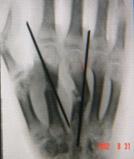

一种骨科常用的内固定材料,其原规格一般固定在二十公分左右,直径在0.5-2毫米间有不同的几种规格。用于固定短小骨折或撕脱骨折等应力不大的骨折固定,也常被用在骨科手术中临时骨折块的固定中。近年来随着外固定支架的广泛应用,克氏针的最大直径逐渐曾加到4毫米,配合外固定锁钉来固定骨盆骨折、跟骨骨折等应急较大的骨折。